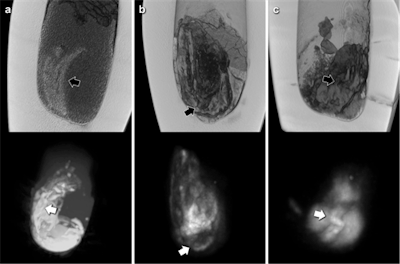

CT reconstructions (top) and correlative maximum intensity projections of MRI scans (bottom) of the three canopic jars with solid contents. Black arrows (CT) and white arrows (MRI) indicate corresponding structures of organ fragment like morphology, probably intestine.The thickness and high density of the calcite mineral of the canopic jars limited x-ray image contrast. CT scans showed few artifacts and revealed hyperdense structures of organ-specific morphology, surrounded by a hypodense homogeneous material. CT scans revealed all the jars were partially filled with material of mostly heterogeneous density (mean 208 Hounsfield units [HU]).

In one jar (jar 607), structures of distinct longitudinal morphology and higher density (mean 344 HU, range from 71 HU to 595 HU) were clearly distinguishable from a homogeneous surrounding material of lower density (mean 186 HU, range from -88 HU to 448 HU).

The low amount of water present in the desiccated jar contents limited image quality of MRI scans. Nevertheless, areas of pronounced signal intensity coincided well with hyperdense structures previously identified on CT scans, according to the researchers. CT-based volumetric calculations revealed holding capacities of the jars of 626 cm3 to 1,319 cm3 and content volumes of 206 cm3 to 1,035 cm3.

The CT findings also raise the question of whether the examined canopic jars do hold entire mummified human organs. The structures identified in canopic jar 607 would be far more compatible with a small organ fragment (potentially intestine) rather than an entire mummified organ, they wrote. The MR images corroborate this, and the observed pronounced variations in signal intensity coincide very well with the organ fragment notion.